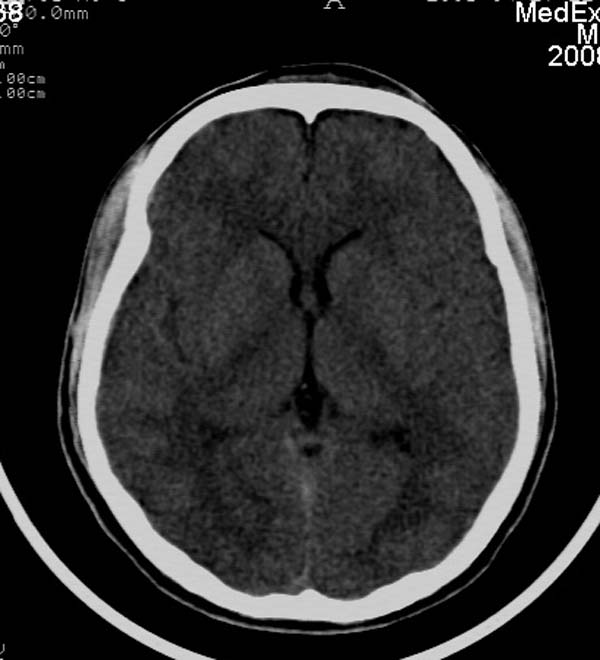

患者,男,24岁。头面部外伤后意识障碍1小时。

小脑幕缘密度增高,考虑有少量出血,建议复查

考虑右侧天幕缘少量蛛网膜下腔出血;建议:必要时复查。

1)考虑少量蛛网膜下腔出血;建议:必要时复查。2)桥前池及左侧环池表皮样囊肿可能。建议:行mri检查。

1)考虑蛛网膜下腔出血;建议:复查。2)桥前池及左侧环池表皮样囊肿可能。建议:行mri检查。

考虑右侧天幕缘区域少量蛛网膜下腔出血。

一侧密度增高,是否考虑为硬膜下血肿,前额血肿真好对冲伤,桥小脑脚增宽建议进一步检查

蛛网膜下腔出血,没问题